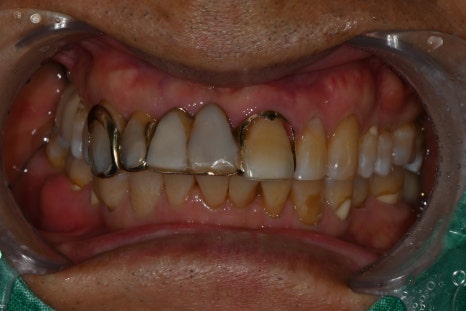

In this patient’s case as well, tartar removal and

periodontal treatment were performed first.

Only after reducing gum inflammation and improving bleeding can the implant settle in a stable way.

Prosthetic Treatment and the Final Steps

The final stage of implant treatment is the prosthesis.

The prosthesis is

The part that functions as the actual tooth,

and it is made to match the patient’s bite and shape.

In this case,

a custom abutment and a zirconia crown were used.